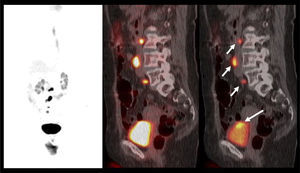

La capacidad de las imágenes moleculares de detectar recidiva de manera más precoz que las imágenes morfológicas como la TC, especialmente en áreas con anatomía alterada por la cirugía y/o radioterapia, ha impulsado el uso del PET/CT en estos pacientes. La vasta experiencia en PET/CT utilizando C11 o F18-Colina ha permitido acumular evidencia suficiente para poder incluirlo en las guías clínicas actuales (16). Sin embargo, otros radiotrazadores nuevos como el Ga68-PSMA, que han presentado un desarrollo explosivo gracias a su alto rendimiento diagnóstico, aún mayor que el del PET/CT con Colina, especialmente a niveles bajos de APE, hacen pensar que prontamente las guías clínicas lo incorporarán en sus sugerencias (27) (Figura 8).

En un grupo de pacientes operados que presentaron posteriormente recidiva bioquímica, Morigi et al (26) demostró una significativa mayor sensibilidad del PET/CT Ga68-PSMA comparado al PET/CT F18-Colina para niveles de APE bajos, lo que estaría explicado en parte por la mejor resolución de contraste del Ga68-PSMA, proporcionando una relación lesión/fondo tres veces mayor respecto a F18-Colina. Ellos obtuvieron una sensibilidad de 50% con APE <0.5ng/ml, 69% con APE 0.5-2.0ng/ml y 86% con APE >2.0ng/ml, vs 13%, 31% y 57% para F18-Colina, respectivamente.

Resultados similares exhiben Eiber et al en un análisis de 248 pacientes con alza del APE post prostatectomía radical, con una sensibilidad de 57.9% con APE <0.5ng/ml, 72.7% con APE 0.5-1.0ng/ml, 93.0% con APE 1-2ng/ml, y 96.8% con APE >2.0ng/ml (28).